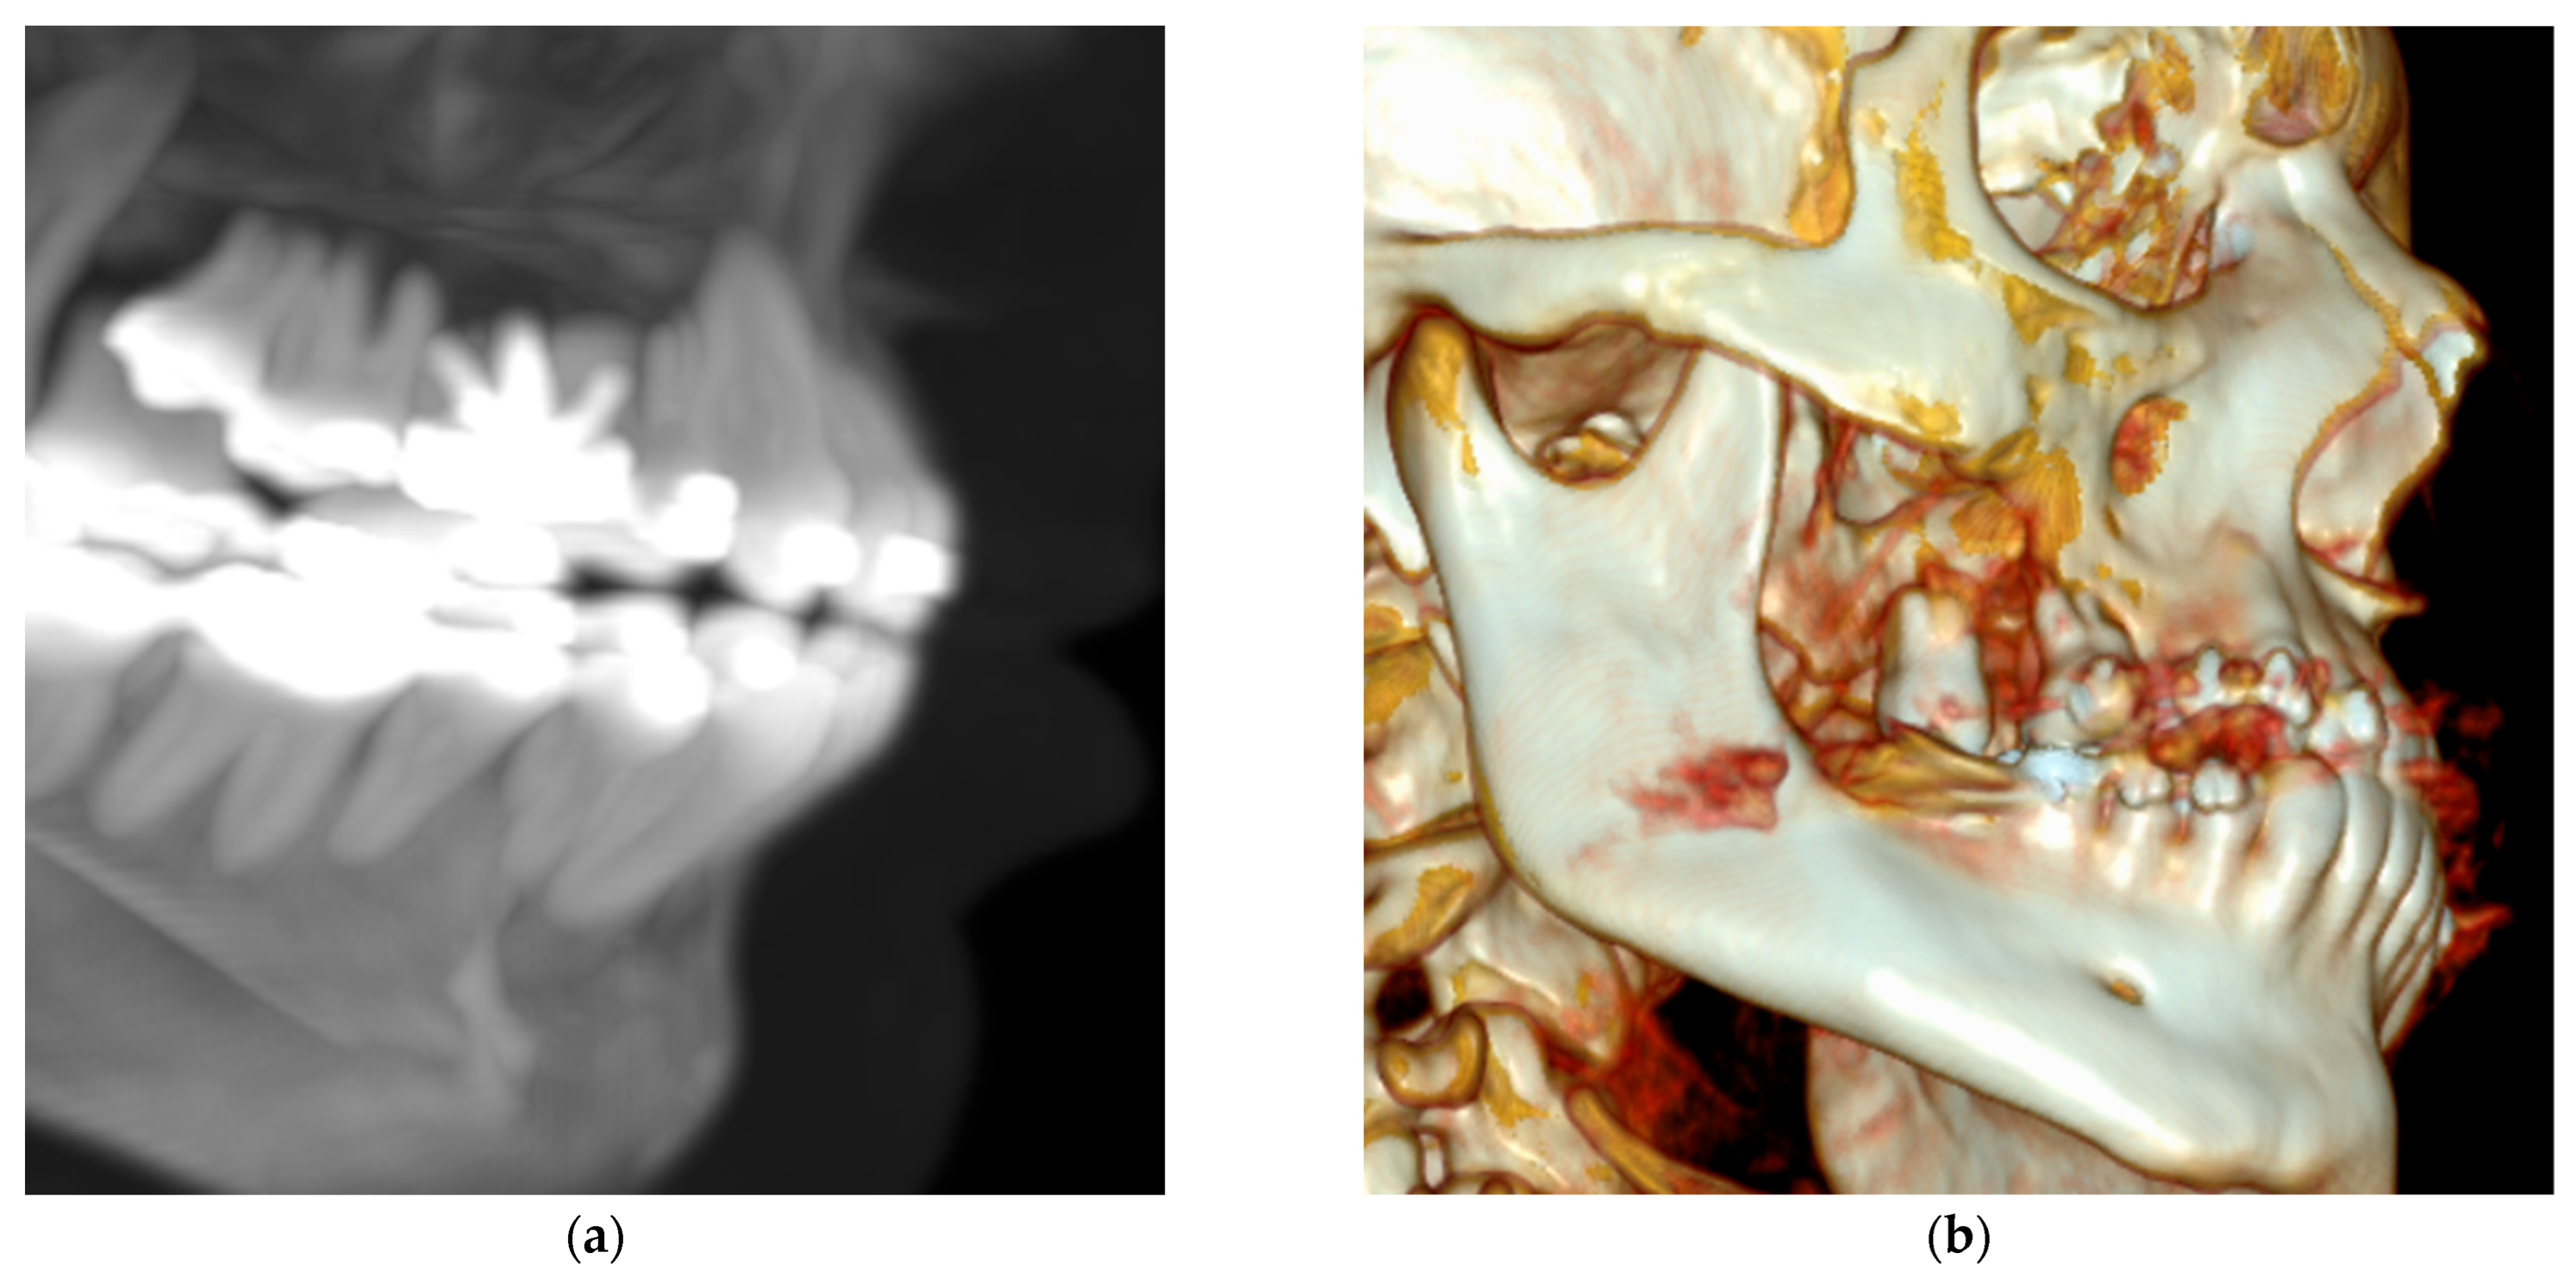

Figure 3.

Contrast-enhanced computed tomography (a) Three-dimensional reconstruction with MIP mask showing the endodontic treatment performed on the upper first molar. (b) Three-dimensional reconstruction showing bone loss/erosion in the right maxilla, primarily affecting the molars.